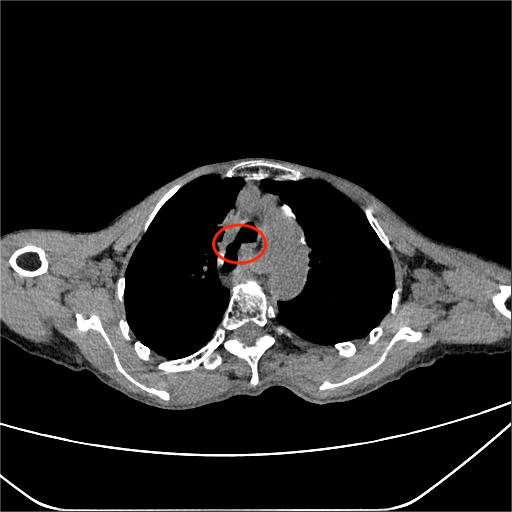

术前食管气管瘘

急诊医生第一时间为朱阿姨安排了全面检查,结果让人揪心:胸部CT提示两肺炎症、心包积液,结合其食管癌术后病史,高度怀疑“食管气管瘘”!血常规检查显示,她的白细胞计数12.95×10⁹/L(正常参考值3.5-9.5×10⁹/L),中性粒细胞百分数94.63%(正常参考值40-75%),降钙素原1.70ng/mL(正常参考值<0.05ng/mL),各项指标均指向严重感染。更危急的是,血气分析显示她的氧分压仅71.0mmHg,已出现I型呼吸衰竭。

首先是吻合口的长期隐患。食管吻合口是食管癌术后食管与其他消化道器官连接的“接口”,本身就是薄弱环节。朱阿姨今年5月就查出吻合口多发溃疡,长期的溃疡不断侵蚀周围组织,逐渐破坏食管壁,而食管与气管距离极近,最终溃疡穿透食管壁,与气管“打通”形成瘘口。

其次,术后纵隔结构改变增加了诊治难度。食管癌手术会改变胸腔内正常的解剖结构,像朱阿姨这样的食道癌根治术后“胸腔胃”,纵隔内组织还可能出现粘连,导致瘘口位置隐蔽,常规检查难以精准定位。